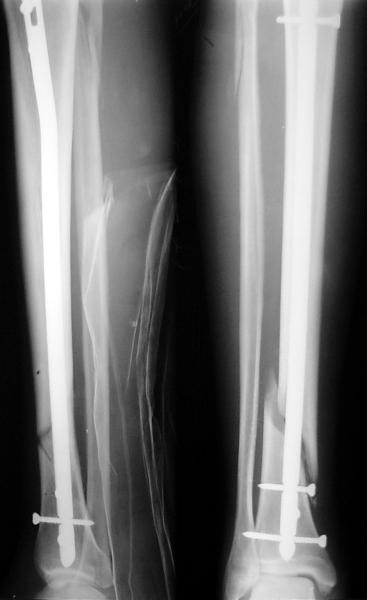

Ok. А также и следующий, в 3 месяца.

Это наглядная демонстрация возможности ранней полной нагрузки при нестабильном по оси повреждении, причем не в самых благоприятных механических условиях - при плохом сопоставлении, со слабым фиксатором.

JOM> Ваш больной имеет счастье, что первым согнулся проксимальный

JOM> замыкающий винт, а не дистальный и гвоздь не пенетрировал

Это не счастье, а тонкий инженерный расчет ;-))

Сверху - один статический винт, а снизу - три. Что раньше сломается? Конечно, он потом и нижние сломал, и Вы правы, если бы верхний динамичесий винт уже уперся бы в нижний край отверстия, будь гвоздь подлинее, перфорировал бы сустав как пить дать.

Как я уже говорил, мы сделали выводы из этого и других подобных случаев. Очевидно, решений проблемы два - либо уменьшить нагрузку, либо увеличить прочность фиксатора. Первое решение работает не со всеми больными, так что пошли по второму пути - мы больше не используем гвозди с запирающими винтами диаметром 4 мм.